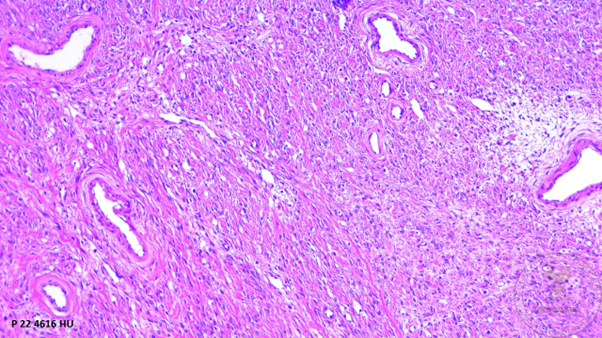

Histological images

1. Panoramic view of the ovary showing the ovarian capsule, proliferation of bundles of spindle cells surrounded by a collagenous stroma accompanied by medium-caliber vessels. (HYE, 4x).

1. Proliferation of bundles of spindle cells surrounded by a collagenous stroma (H&E 10x).

1. Spindle-shaped cells with ovoid nuclei with pointed ends and scant eosinophilic cytoplasm with the presence of lipid inclusions that mixes with the surrounding eosinophilic stroma (HYE 40x).